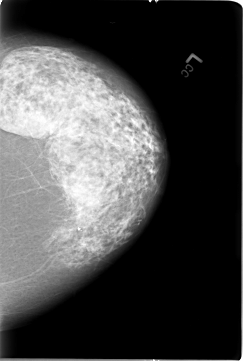

B_3026_1.RIGHT_MLO

B_3026_1.LEFT_MLO

B_3026_1.RIGHT_CC

B_3026_1.LEFT_CC

ics_version 1.0

filename B-3026-1

DATE_OF_STUDY 8 3 1995

PATIENT_AGE 75

FILM

FILM_TYPE REGULAR

DENSITY 3

DATE_DIGITIZED 22 7 1997

DIGITIZER LUMISYS LASER

LEFT_CC LINES 5768 PIXELS_PER_LINE 3880 BITS_PER_PIXEL 12 RESOLUTION 50 NON_OVERLAY

LEFT_MLO LINES 5728 PIXELS_PER_LINE 4112 BITS_PER_PIXEL 12 RESOLUTION 50 NON_OVERLAY